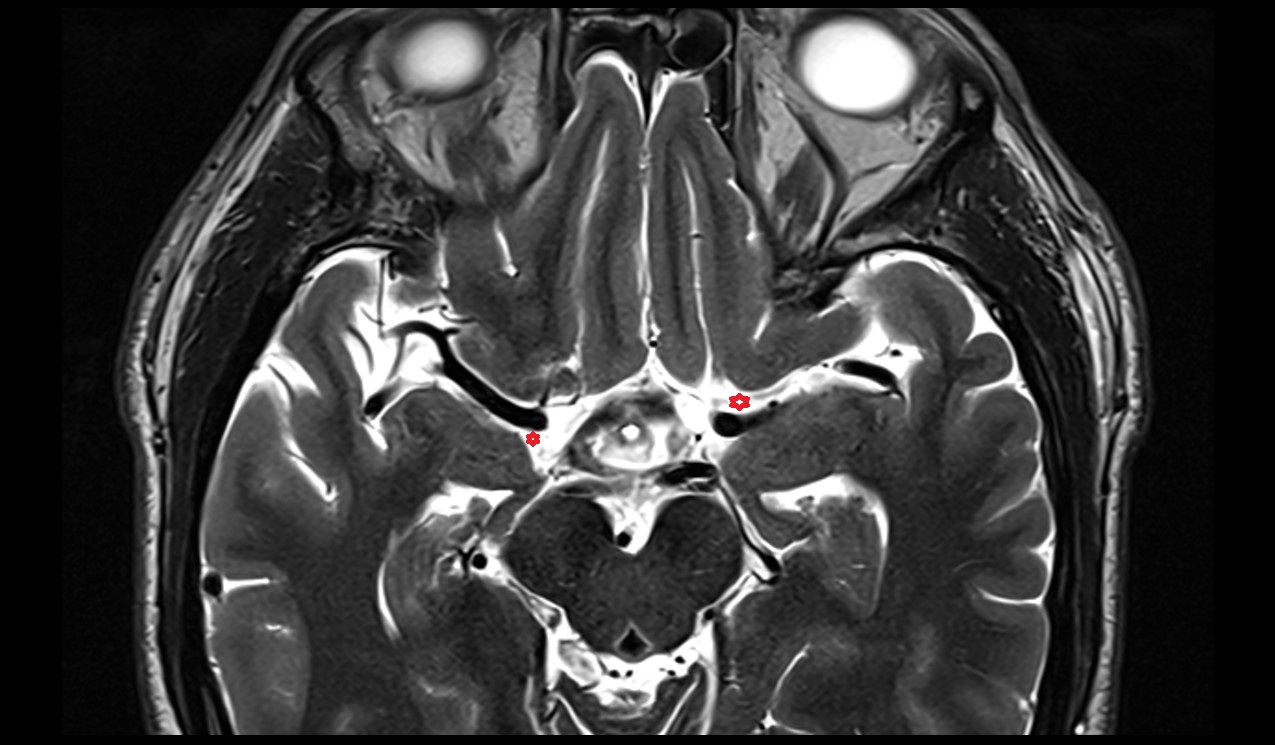

- Median aperture of fourth ventricle (foramen of Magendie)